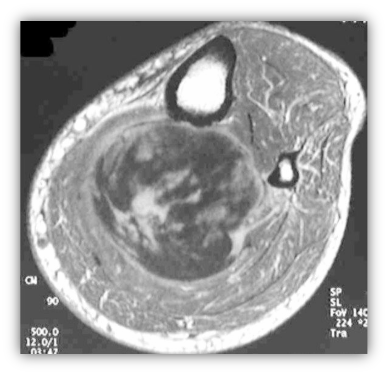

Η Μυοσκελετική Ογκολογία ασχολείται με την διάγνωση και την αντιμετώπιση των καλοήθων και κακοήθων όγκων των οστών και των μαλακών μορίων όταν εντοπίζονται στα άκρα.

Η απεικόνιση των βλαβών πρέπει να κατευθύνεται από τον Ορθοπαιδικό Χειρουργό και ακολουθεί μία συγκεκριμένη μεθοδολογία.